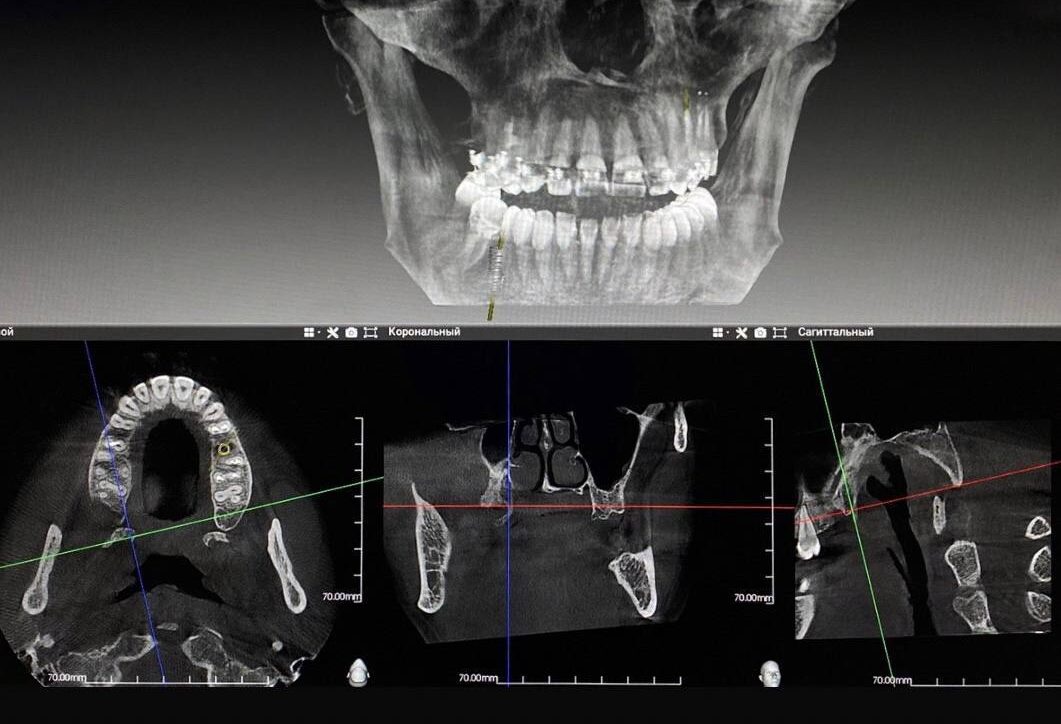

В последние годы качество и эффективность стоматологического лечения существенно выросли. Ключевая роль в этом принадлежит 3D технологиям диагностики. Рентген каждого отдельного зуба теперь можно заменить одномоментным панорамным снимком КТ. Там, где раньше нужно было тратить время и ресурсы на изготовление слепка, теперь вопрос решает 3D-сканирование. Лечение зубов под микроскопом позволяет не только выявить на ранней стадии кариес, малейшие трещинки и свести к минимуму травматизм здоровых тканей, но и обеспечить лучший результат лечения под многократным увеличением. Мы в Aesculap инвестируем в 3D-технологии для того, чтобы ваши усилия по восстановлению здоровой и красивой улыбки приносили не только результат, но и удовольствие от процесса.

Современная стоматология гораздо более эффективна, чем 5, 10, 15 лет назад благодаря инновационным чувствительным методам диагностики и терапии. Для того чтобы изучить анатомию зуба и челюсти, разработать детальный план лечения, стоматологи в Aesculap используют рентген, цифровой сканер, а также панорамную КТ-диагностику на одном из лучших томографов в мире GENORAY PAPAYA 3D PLUS. Компьютерная диагностика зубов позволяет снять все необходимые для лечения параметры за один сеанс и предложить пациенту максимально эффективный план санации полости рта. Снимок позволяет определить очаги патологий, состояние корней и зубных каналов, верхнечелюстных и дополнительных пазух носа, мягких тканей нижней и верхней челюстей, оценить жизнеспособность каждого зуба, в частности, молочные зубы и позиции зачатков у детей.